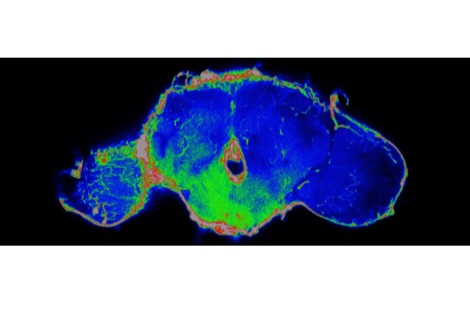

لإنشاء شاشة عرض حية، قام الباحثون بتعديل الخلايا الجذعية للبشرة وراثيًا بحيث تستجيب لإشارات الالتهاب داخل الجسم. عند تنشيط مسار رئيسي مرتبط بالالتهاب، يُعرف باسم NF-κB، تُنتج الخلايا المُهندسة بروتينًا فلوريًا أخضر.

ثم استُخدمت هذه الخلايا المُعدّلة لزراعة أنسجة جلدية، زُرعت على فئران. بعد التئام الطعوم واندماجها مع الأنسجة المحيطة، تصرفت البشرة المُهندسة بشكل مشابه للبشرة الطبيعية، باستثناء فرق جوهري واحد. فعندما يحدث التهاب داخل الجسم، تبدأ المنطقة المزروعة بالتوهج باللون الأخضر.

يُترجم هذا التوهج إشارة جزيئية غير مرئية إلى إشارة مرئية، مما يسمح بقراءة النشاط البيولوجي الداخلي مباشرةً على سطح الجلد. ولأن المستشعر مصنوع من خلايا جذعية حية، فهو لا يعتمد على الإلكترونيات أو مصادر الطاقة أو الاستبدال الدوري. ومع تجدد الجلد بشكل طبيعي، تستمر الخلايا الجذعية المُهندسة في إنتاج خلايا استشعار جديدة.

وقال شوجي تاكيوتشي من جامعة طوكيو في بيان صحفي: "على عكس الأجهزة التقليدية التي تتطلب مصادر طاقة أو استبدالًا دوريًا، يُحافظ الجسم نفسه على هذا النظام بيولوجيًا. في تجاربنا، استمرت وظيفة المستشعر لأكثر من 200 يوم، حيث جددت الخلايا الجذعية المُهندسة البشرة باستمرار."